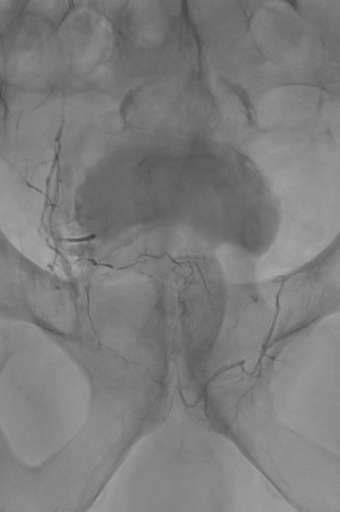

תמונות מהצנתור:

לאחר החסימה:

היעלמות זרימת הדם לערמונית – חסימה מלאה ומדויקת.